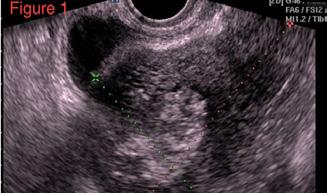

A opera sau a nu opera? Raspunsul ecografistului

Dr. Dan Adrian Stănescu 24